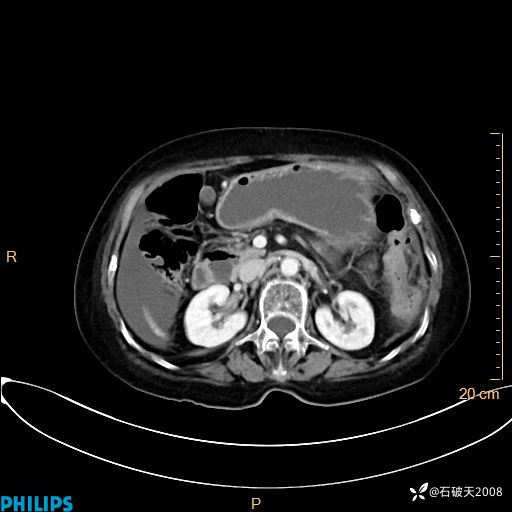

静脉期